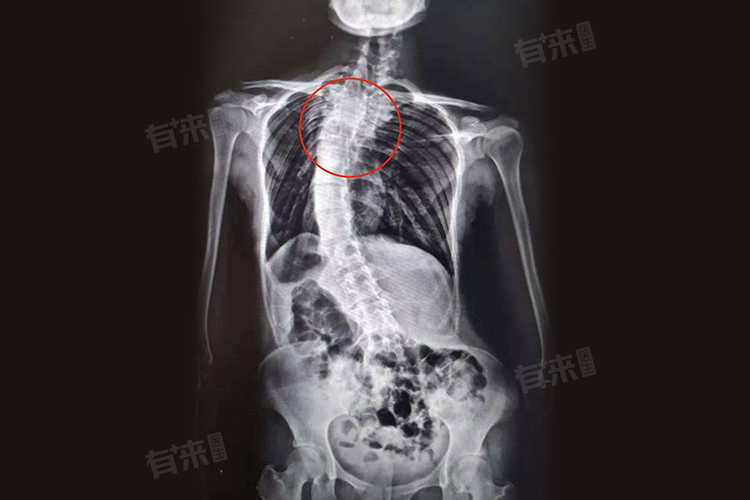

- 脊柱侧弯:在胸椎变形的情况下,脊柱可能逐渐发生侧弯,导致两肩高低不平、脊柱偏离中线等症状,可能进一步加重胸椎的负担,形成恶性循环。